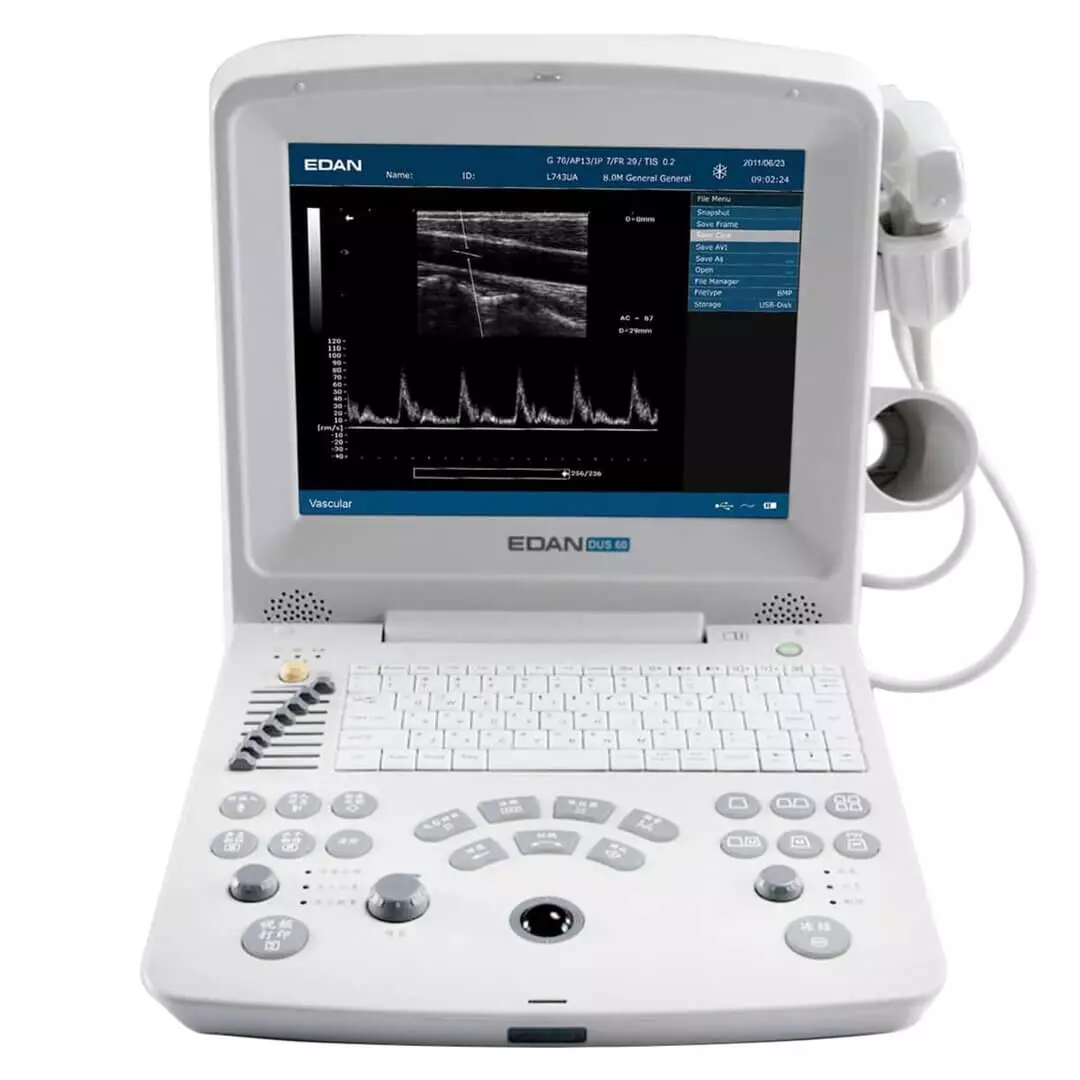

EDAN Échographe DUS 60

Échographe DUS 60 de EDAN

L'échographe DUS 60 de Edan convainc par une qualité d'image optimisée. En outre, le système d'échographie est facile à transporter et peut donc être utilisé à différents endroits. La technologie entièrement numérique de cet appareil permet de voir et d'évaluer les détails les plus infimes. Le clavier de l’échographe DUS 60 est équipé d'un rétroéclairage, ce qui rend l'échographie plus conviviale pour le patient, car l'appareil peut également être utilisé dans une salle d'examen sombre. Les résultats de la fonction Doppler et les images échographiques obtenues sont faciles à interpréter grâce à la fonction multi-pseudo-couleurs.

- Appareil d'échographie mobile avec écran LCD et sonde

- Dimensions : L 33 x l 22 x H 32 cm

- Poids : 7 100 g